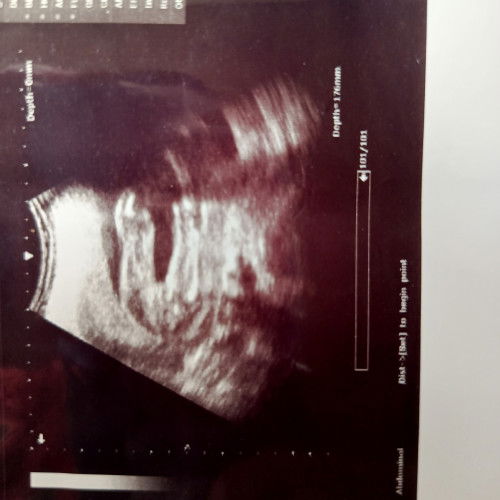

klau girl mcm ni 😅 doctor scan je trus terpampang burger

nampak 3 line mcm girl. nanti try repeat scan lagi sis

mcm girl tu.. hihi

baby girl tu sis

yea sbb nmpk 3 line.sy pun hrp girl kali ni tpi 2 kali scan nmpk pistol 😂

girl

hrap girl ..